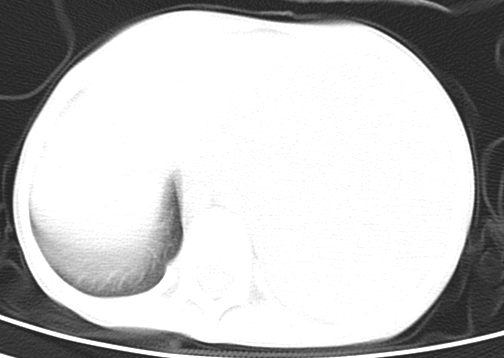

患儿 女 4岁,发热 咳嗽 胸透 考虑:左侧脓胸

左侧胸廓内见大量密实阴影,肺尖部尚有少量肺组织影,纵膈明显受压移位,肋骨未见明显受侵征象,虽然病人年龄较小,但如此大量的“积液”,还是要警惕,不同意一般感染,可结合穿刺脱落细胞学检查。

左侧大量胸腔积液。

左侧大量胸腔积液;建议胸水检查。

左侧张力性大量胸腔积液压迫性肺不张、感染;建议治疗后复查。